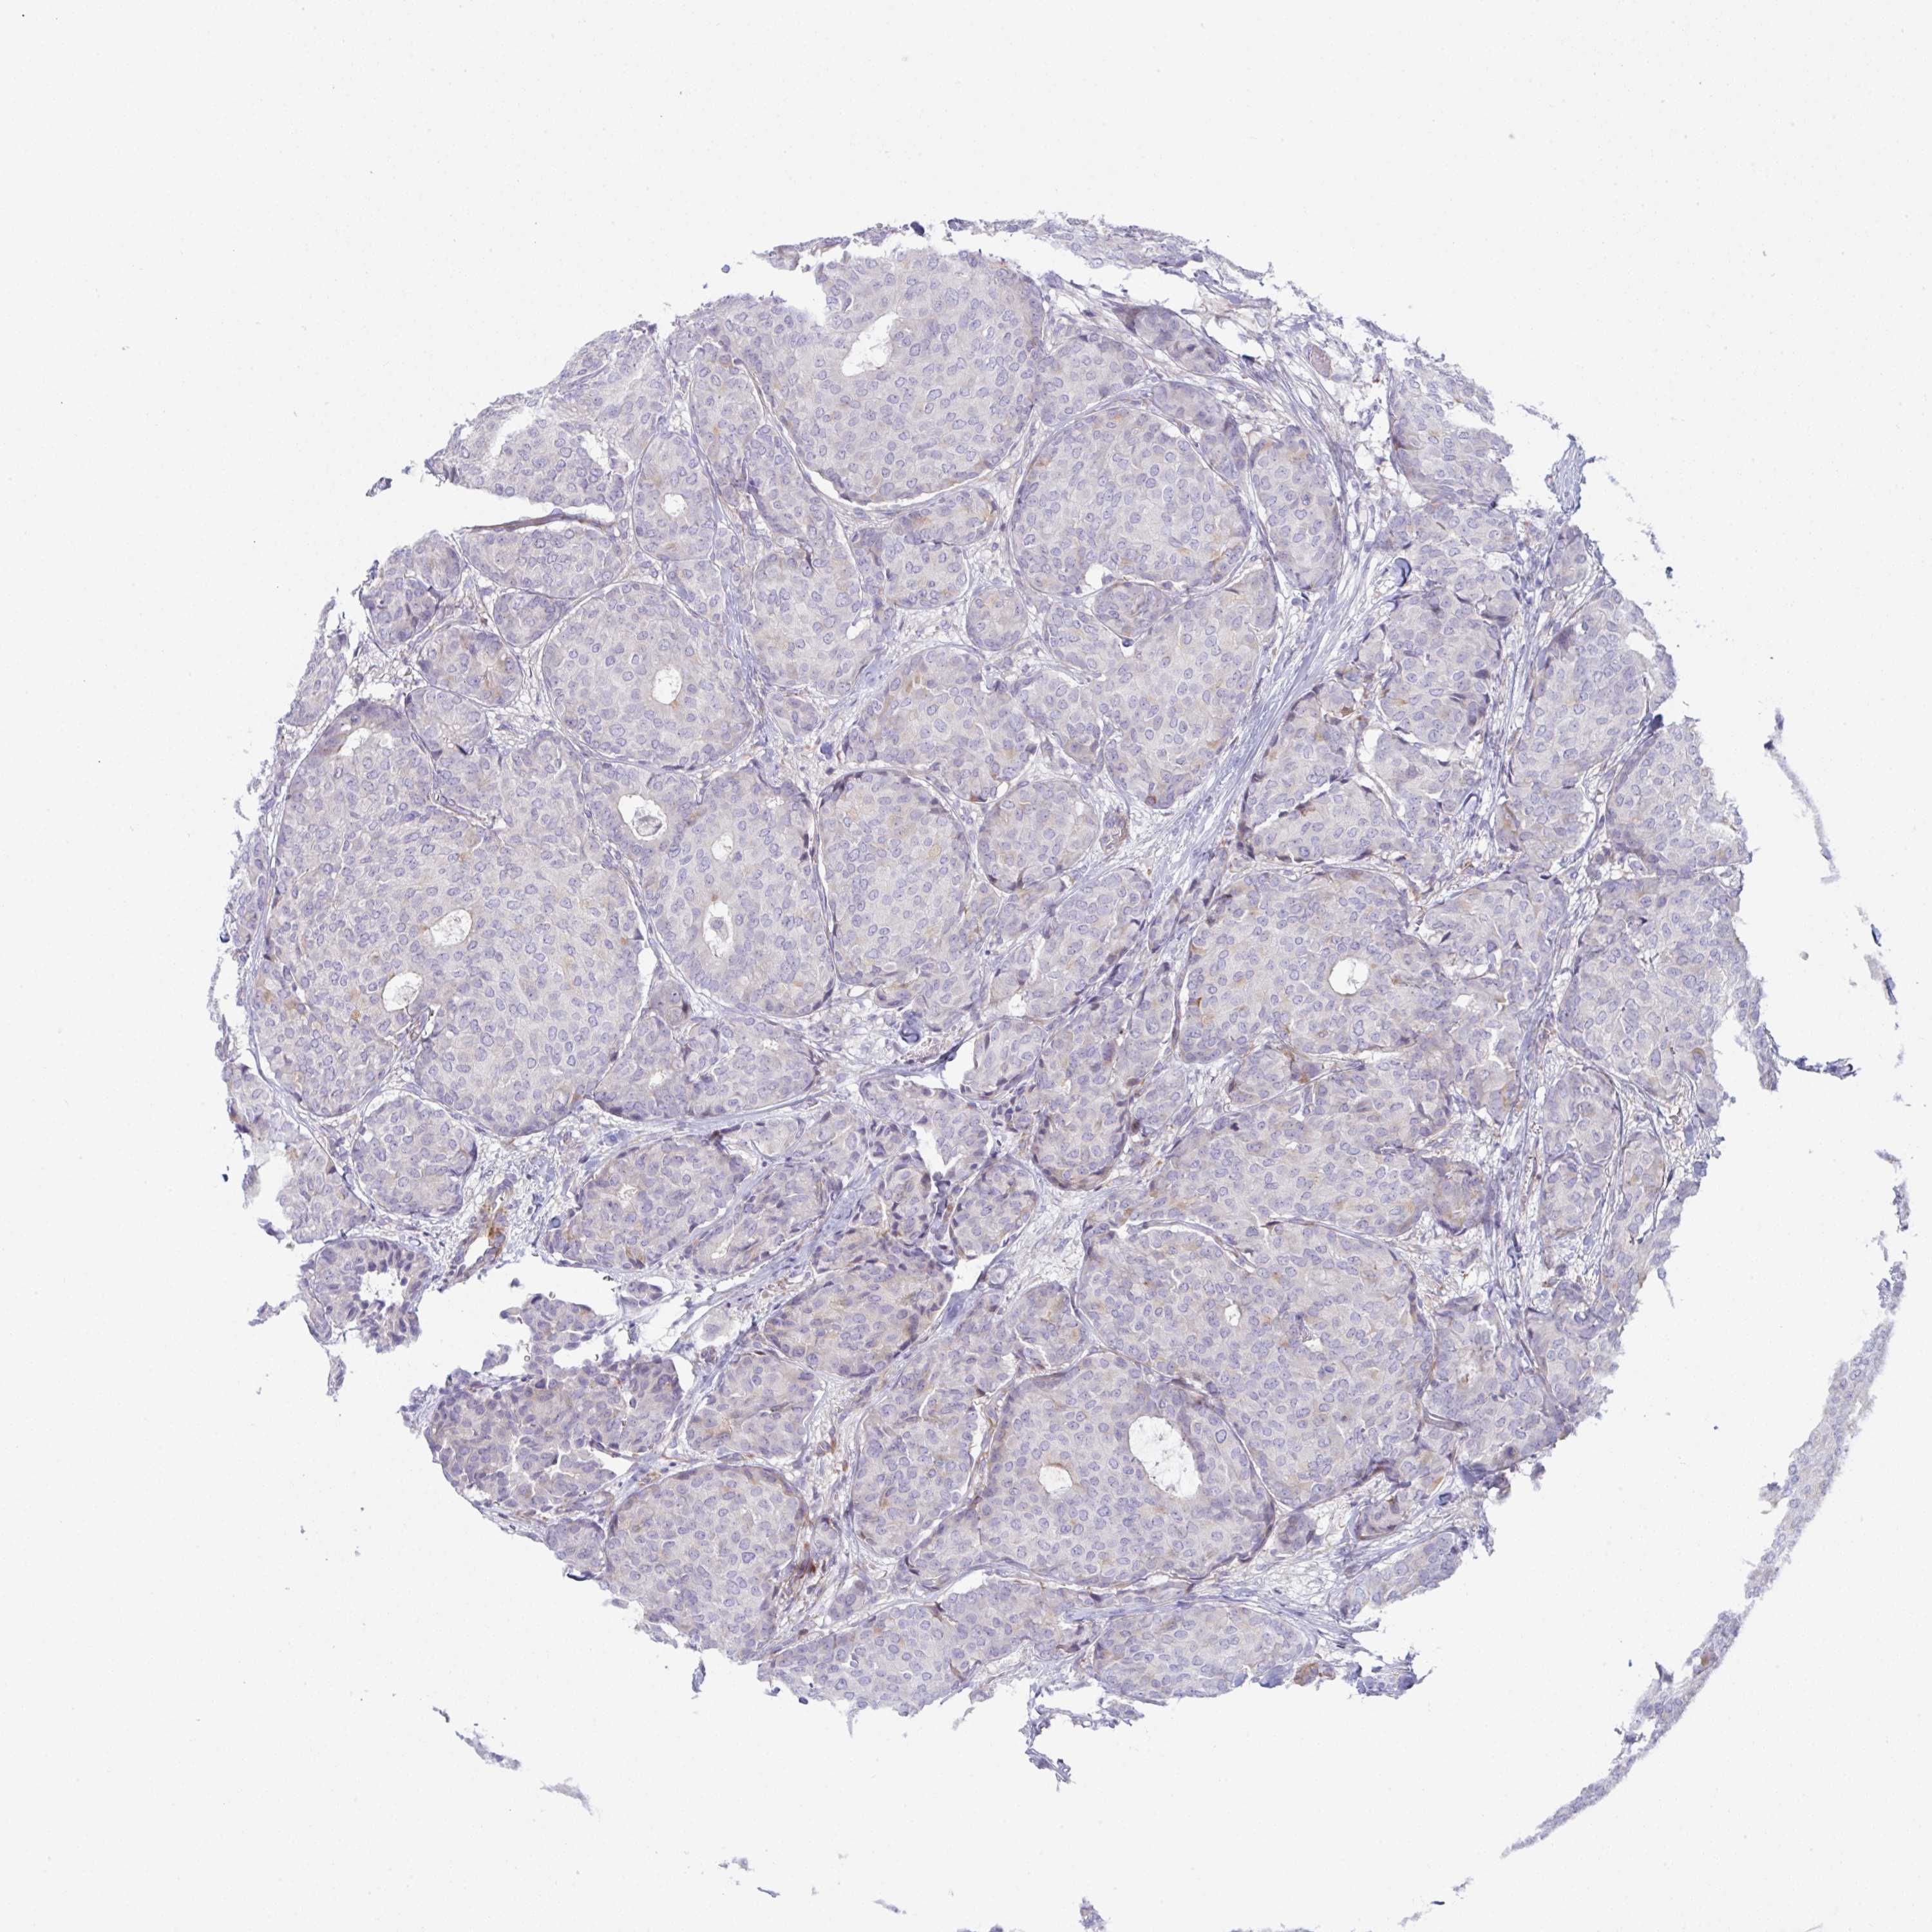

CANCER BREAST CANCER Show tissue menu

BRCA TCGA BRCA VALIDATION PROTEIN EXPRESSION

Breast cancer

Human cancer

Breast invasive carcinoma

ZNF713 is not prognostic in Breast Invasive Carcinoma (TCGA)